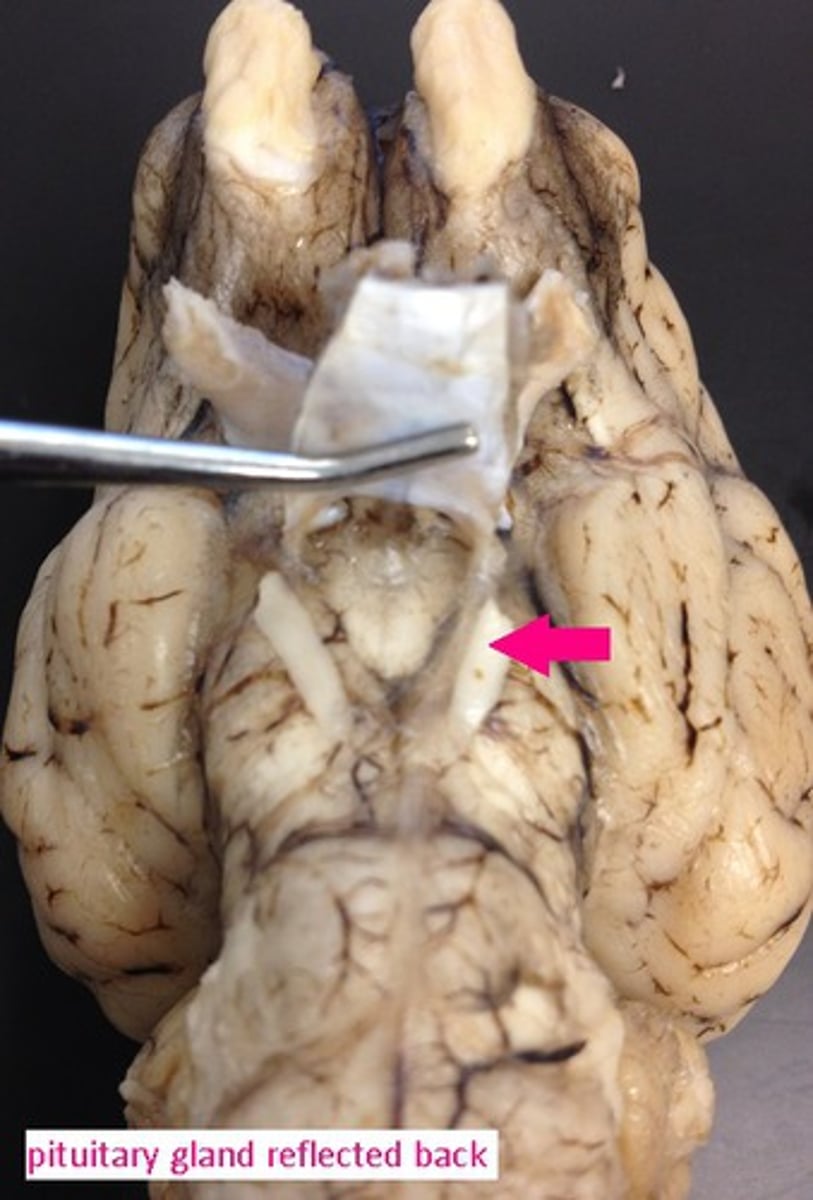

pituitary gland

endocrine gland at the base of the brain

Optic chiasm

Junction at which some fibers from easch optic nerve crisscross, enabling effective binocular vision (#15)

Optic nerve

Connects the retina to the optic chiasm (#16)

Olfactory bulb

Involved in detection and discrimination of odors (#17)